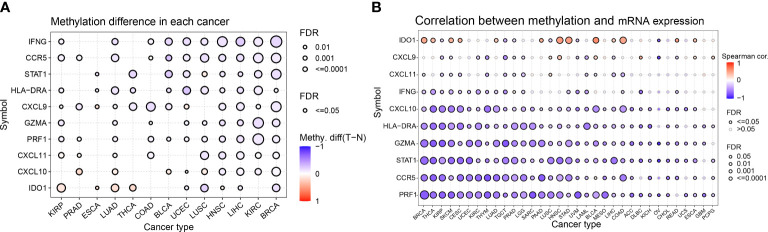

Differential analysis of methylation of IFN-γ-related genes in pan-cancer

Abnormal DNA methylation may lead to abnormal gene expression and an increased risk of cancer. We studied the differential methylation of IFN-γ-related genes in 13 distinct types of cancers to learn more about how these genes impact tumorigenesis and uncover the mechanism of aberrant expression of these genes. IDO1 had high methylation levels in KIRP, LUAD, THCA, and ESCA, and significantly low methylation levels in LUSC and BRCA. Among the 10 genes studied, almost all of them showed low methylation levels in BRCA, KIRC, LIHC, and HNSC. Among 13 kinds of tumors, STAT1, IFNG, and CCR5 showed low methylation levels in BRCA, KIRC, LIHC, HNSC, UCEC, and BLCA (f3). For comprehending the relationship between methylation and IFN-γ mRNA expression, we discovered a strong inverse correlation in 31 cancer subtypes. Methylation was inversely associated with the expression of PRF1, CCR5, STAT1, GZMA, HLA-DRA, and CXCL10 in these malignancies. Conversely, methylation was positively linked to IDO1 expression in BRCA, THCA, SKCM, CESC, LUAD, PAAD, HNSC, STAD, BLCA, LIHC, COAD, READ, and ESCA (f3). These results suggest that the aberrant expression of IFN-γ-related genes is partly due to aberrant methylation regulation.